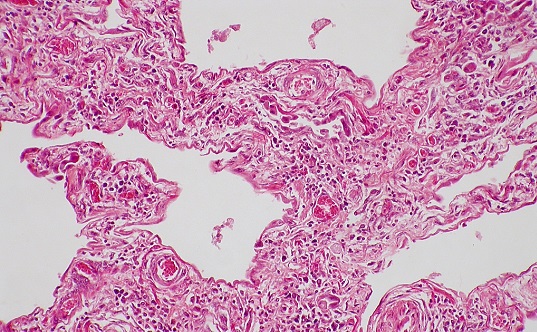

Fibrotic diseases are a group of conditions—often autoimmune—characterized by excessive tissue scarring. They can drastically hinder patients’ quality of life, and in some cases, they can be life-threatening—fibrosis contributes to approximately 45% of all deaths in developed nations. However, there are no effective treatments.

In 2022, the YSM researchers found that skin samples from patients with scleroderma—a rare autoimmune disease that causes fibrosis of the skin and sometimes internal organs—had increased levels of epiregulin, a signaling molecule that binds to EGFR. They hypothesized that more epiregulin could be driving the overactivation of EGFR, leading to fibrosis in scleroderma. To test this idea, they used an antibody to target and reduce epiregulin in animal models and found that it reversed fibrosis.

Then, the team tested their anti-EREG antibody in humanized mouse models and skin biopsies from patients and found that inhibiting epiregulin reduced biomarkers associated with fibrosis. These findings suggest that the therapeutic antibody could be a promising new therapy for patients with various types of fibrotic conditions.